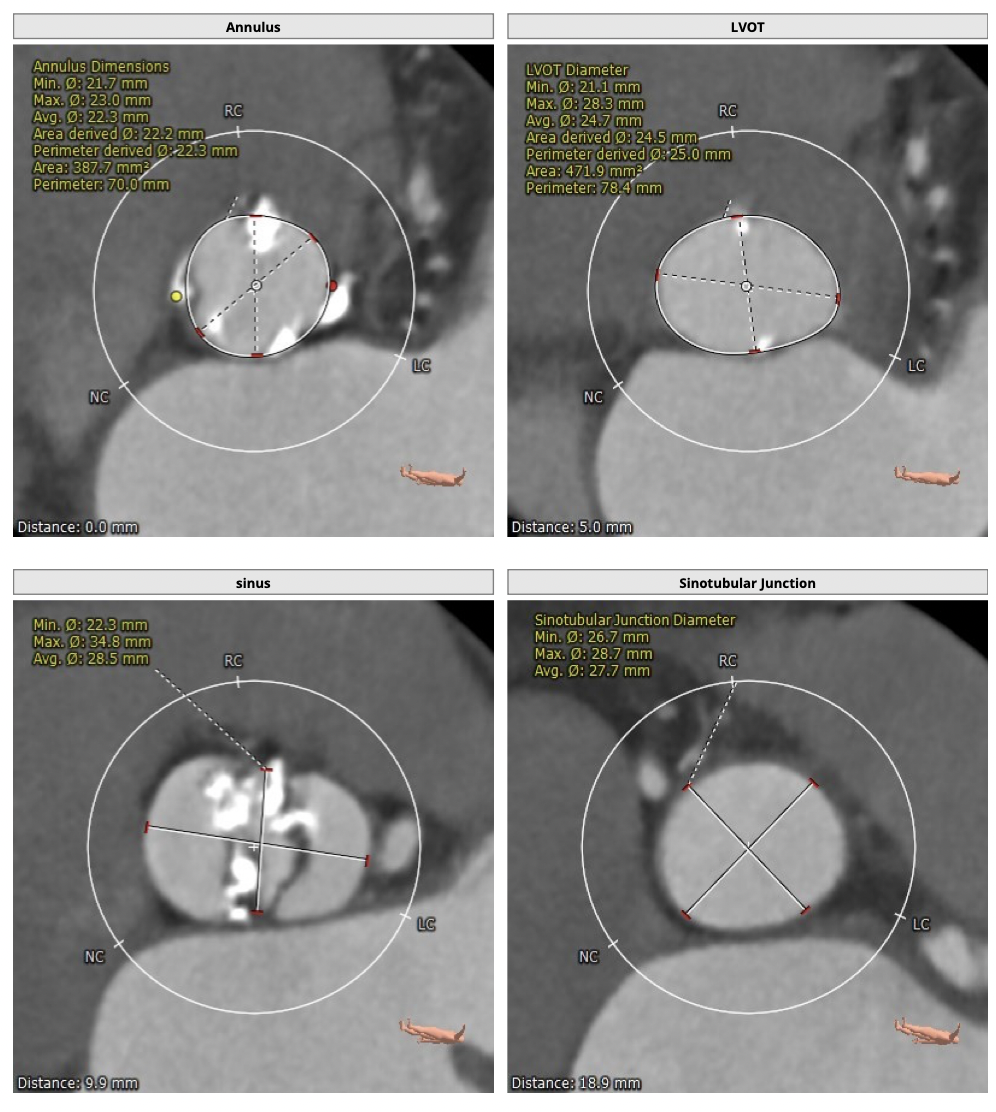

主动脉CT

图片

*功能型二叶瓣,瓣叶增厚,重度钙化,瓣环及左室流出道层面仍可见钙化,左右可见钙化融合,瓣膜释放后发生瓣周漏的风险较高,瓣膜释放后容易移位。

*左右股动脉较细,直径小于6mm, 双侧髂动脉-股动脉走形迂曲,可见明显钙化,术中操作需谨慎轻柔,注意血管并发症的发生。

经分析研判,拟从右侧股动脉穿刺入路,使用22mm球囊预扩,选用L26号的VenusA-Valve瓣膜,采用VenusA-Plus可回收输送系统进一步确保手术安全,瓣膜释放后结合造影和超声情况,决定是否后扩。